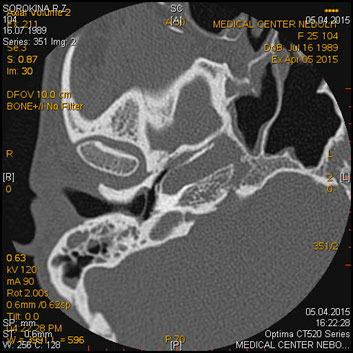

МСКТ височных костей

Показания:

- Воспалительные заболевания и их осложнения

- Травма, аномалии развития

- Опухолевый процесс